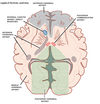

vascular supply of brain

73

blood supply of the brain coronal view

74

blood supply of basal ggl

AChA

AChA 2

PCA